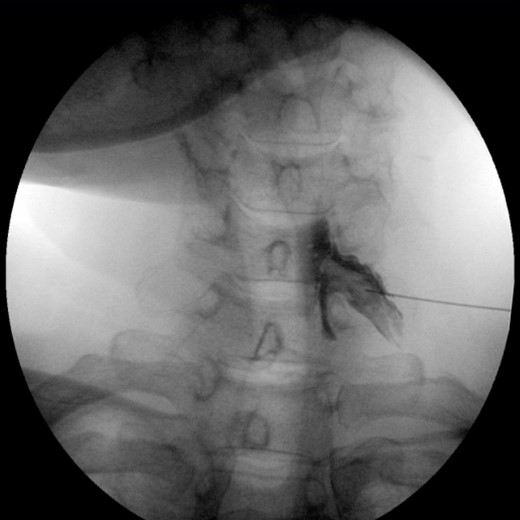

3.0.1 석회쇄척술 (barbotage)

석회쇄철술 후 사진, 시술 사진 추가